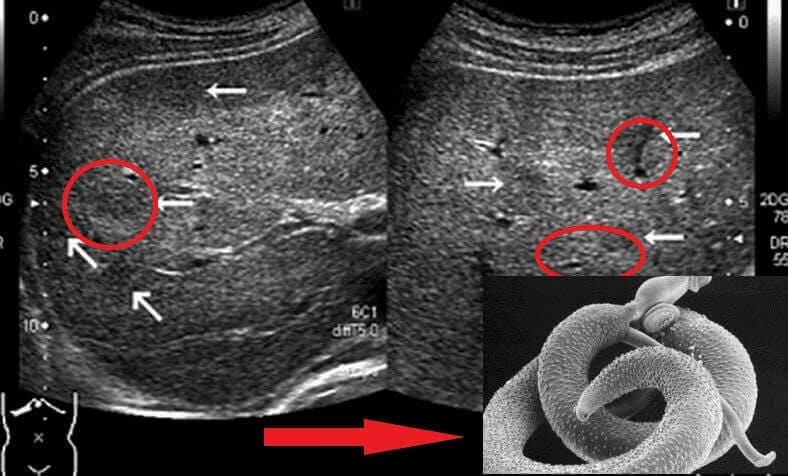

În timpul autopsiei, s-a descoperit că avea paraziți în aproape tot corpul: în stomac, în ficat, chiar și în inimă... Era teribil de înfricoșător!

Urme de paraziți în stomac

La cabinet mi s-a spus că în 95% din cazuri, paraziții sunt adevărata cauză a acestor excrescențe.